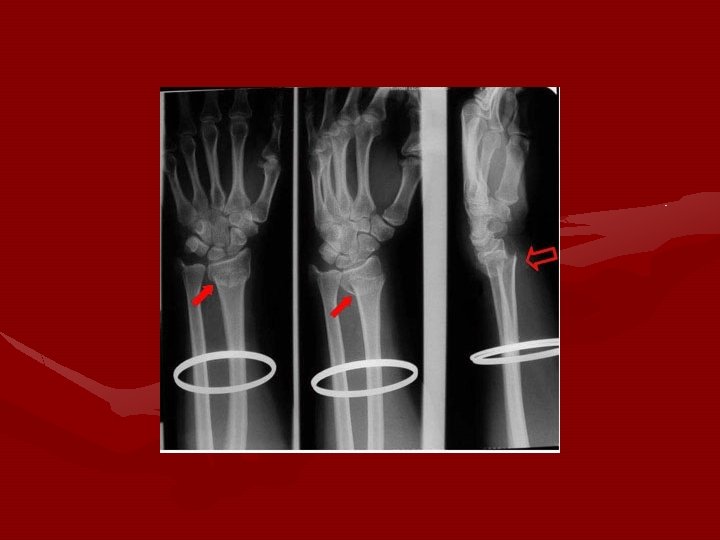

Dislocation of Lunate • MXN: • Forced hyperextension of wrist

Lunate dislocation